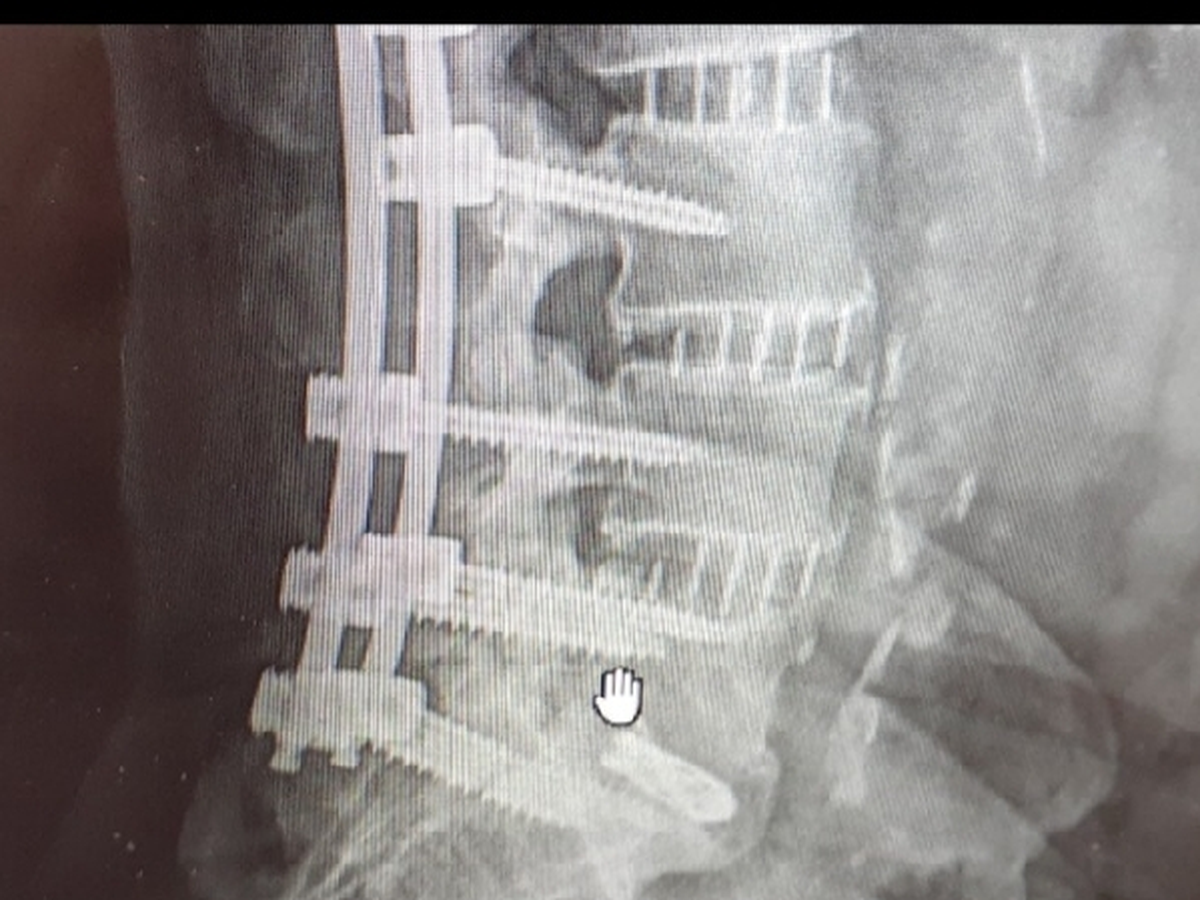

My name is tattoo dave and been working my own shop for 35 years,a drunk driver hit me and ruined my life,all I have left is to pay the balance on my home which I am leaving to my special needs son when I leave this world. Can not work anymore due to broken screws in my back and need help to save my home which is almost paid off.